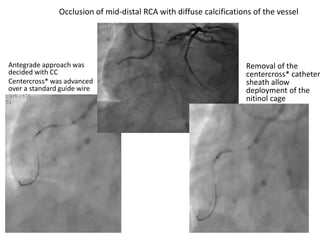

Antegrade approach was

decided with CC

Centercross* was advanced

over a standard guide wire

Removal of the

centercross* catheter

sheath allow

deployment of the

nitinol cage

Occlusion of mid-distal RCA with diffuse calcifications of the vessel